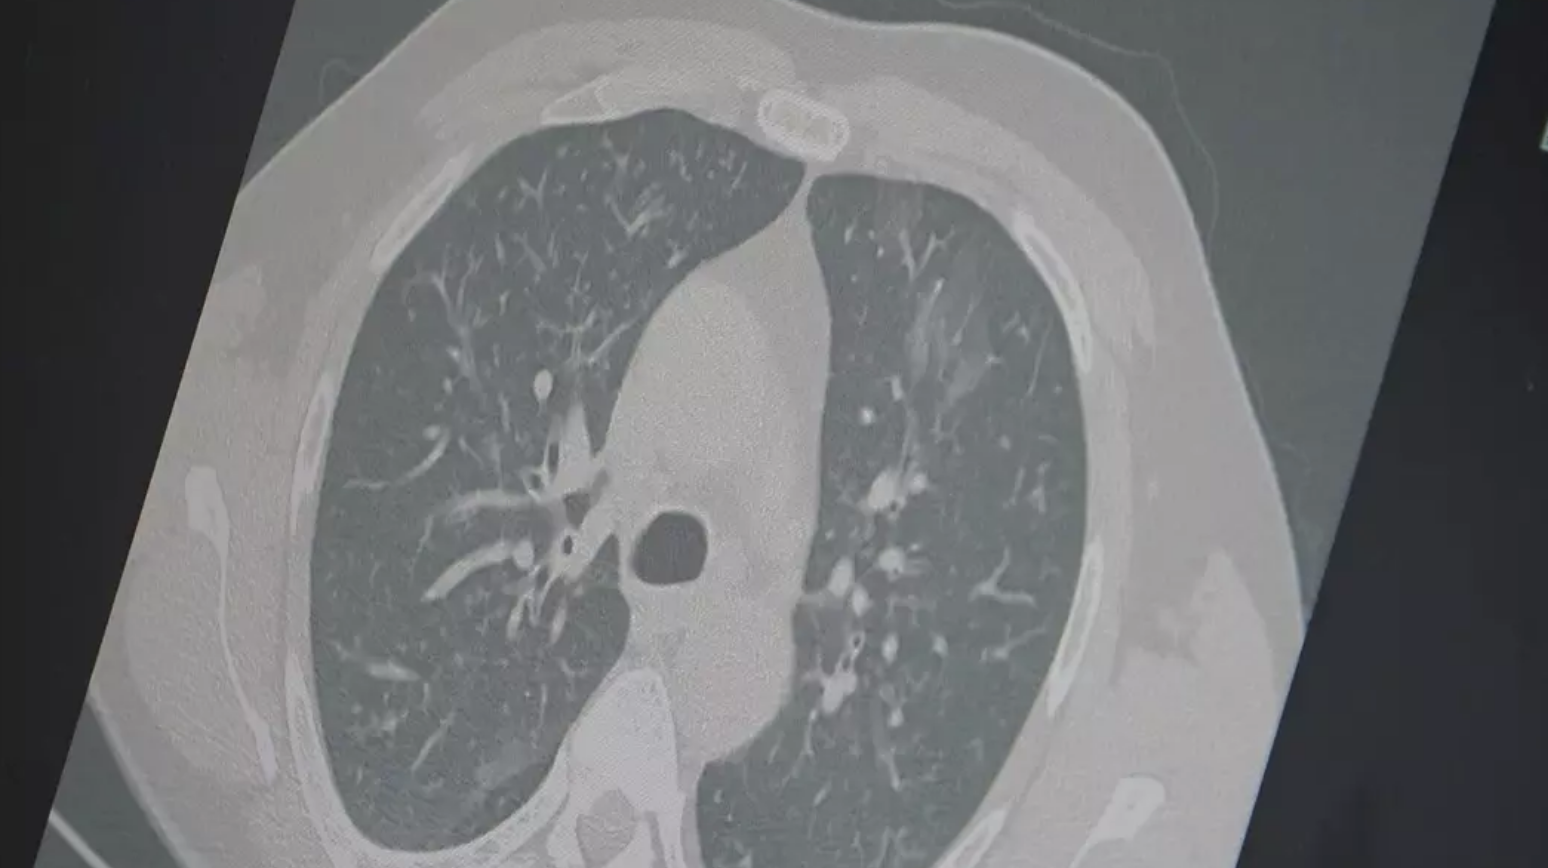

Dr. Özkaya, grip ve kovid 19'un zatürreye dönüşme riski taşıdığını vurgulayarak, "Grip veya kovid sonrası birçok hastamızda hastalık akciğerlere iniyor ve zatürre olarak karşımıza çıkıyor. Hastaneye yatan hasta sayısında da artış gözlemliyoruz" şeklinde konuştu.

"En ufak grip benzeri şikayeti olan vatandaşlarımızın evlerinde dinlenmelerini öneriyoruz. Uzamış öksürük ve nefes darlığı yaşayanların ise mutlaka doktora başvurarak akciğer röntgeni çektirmeleri ve uygun tedaviyi almaları gerekiyor."